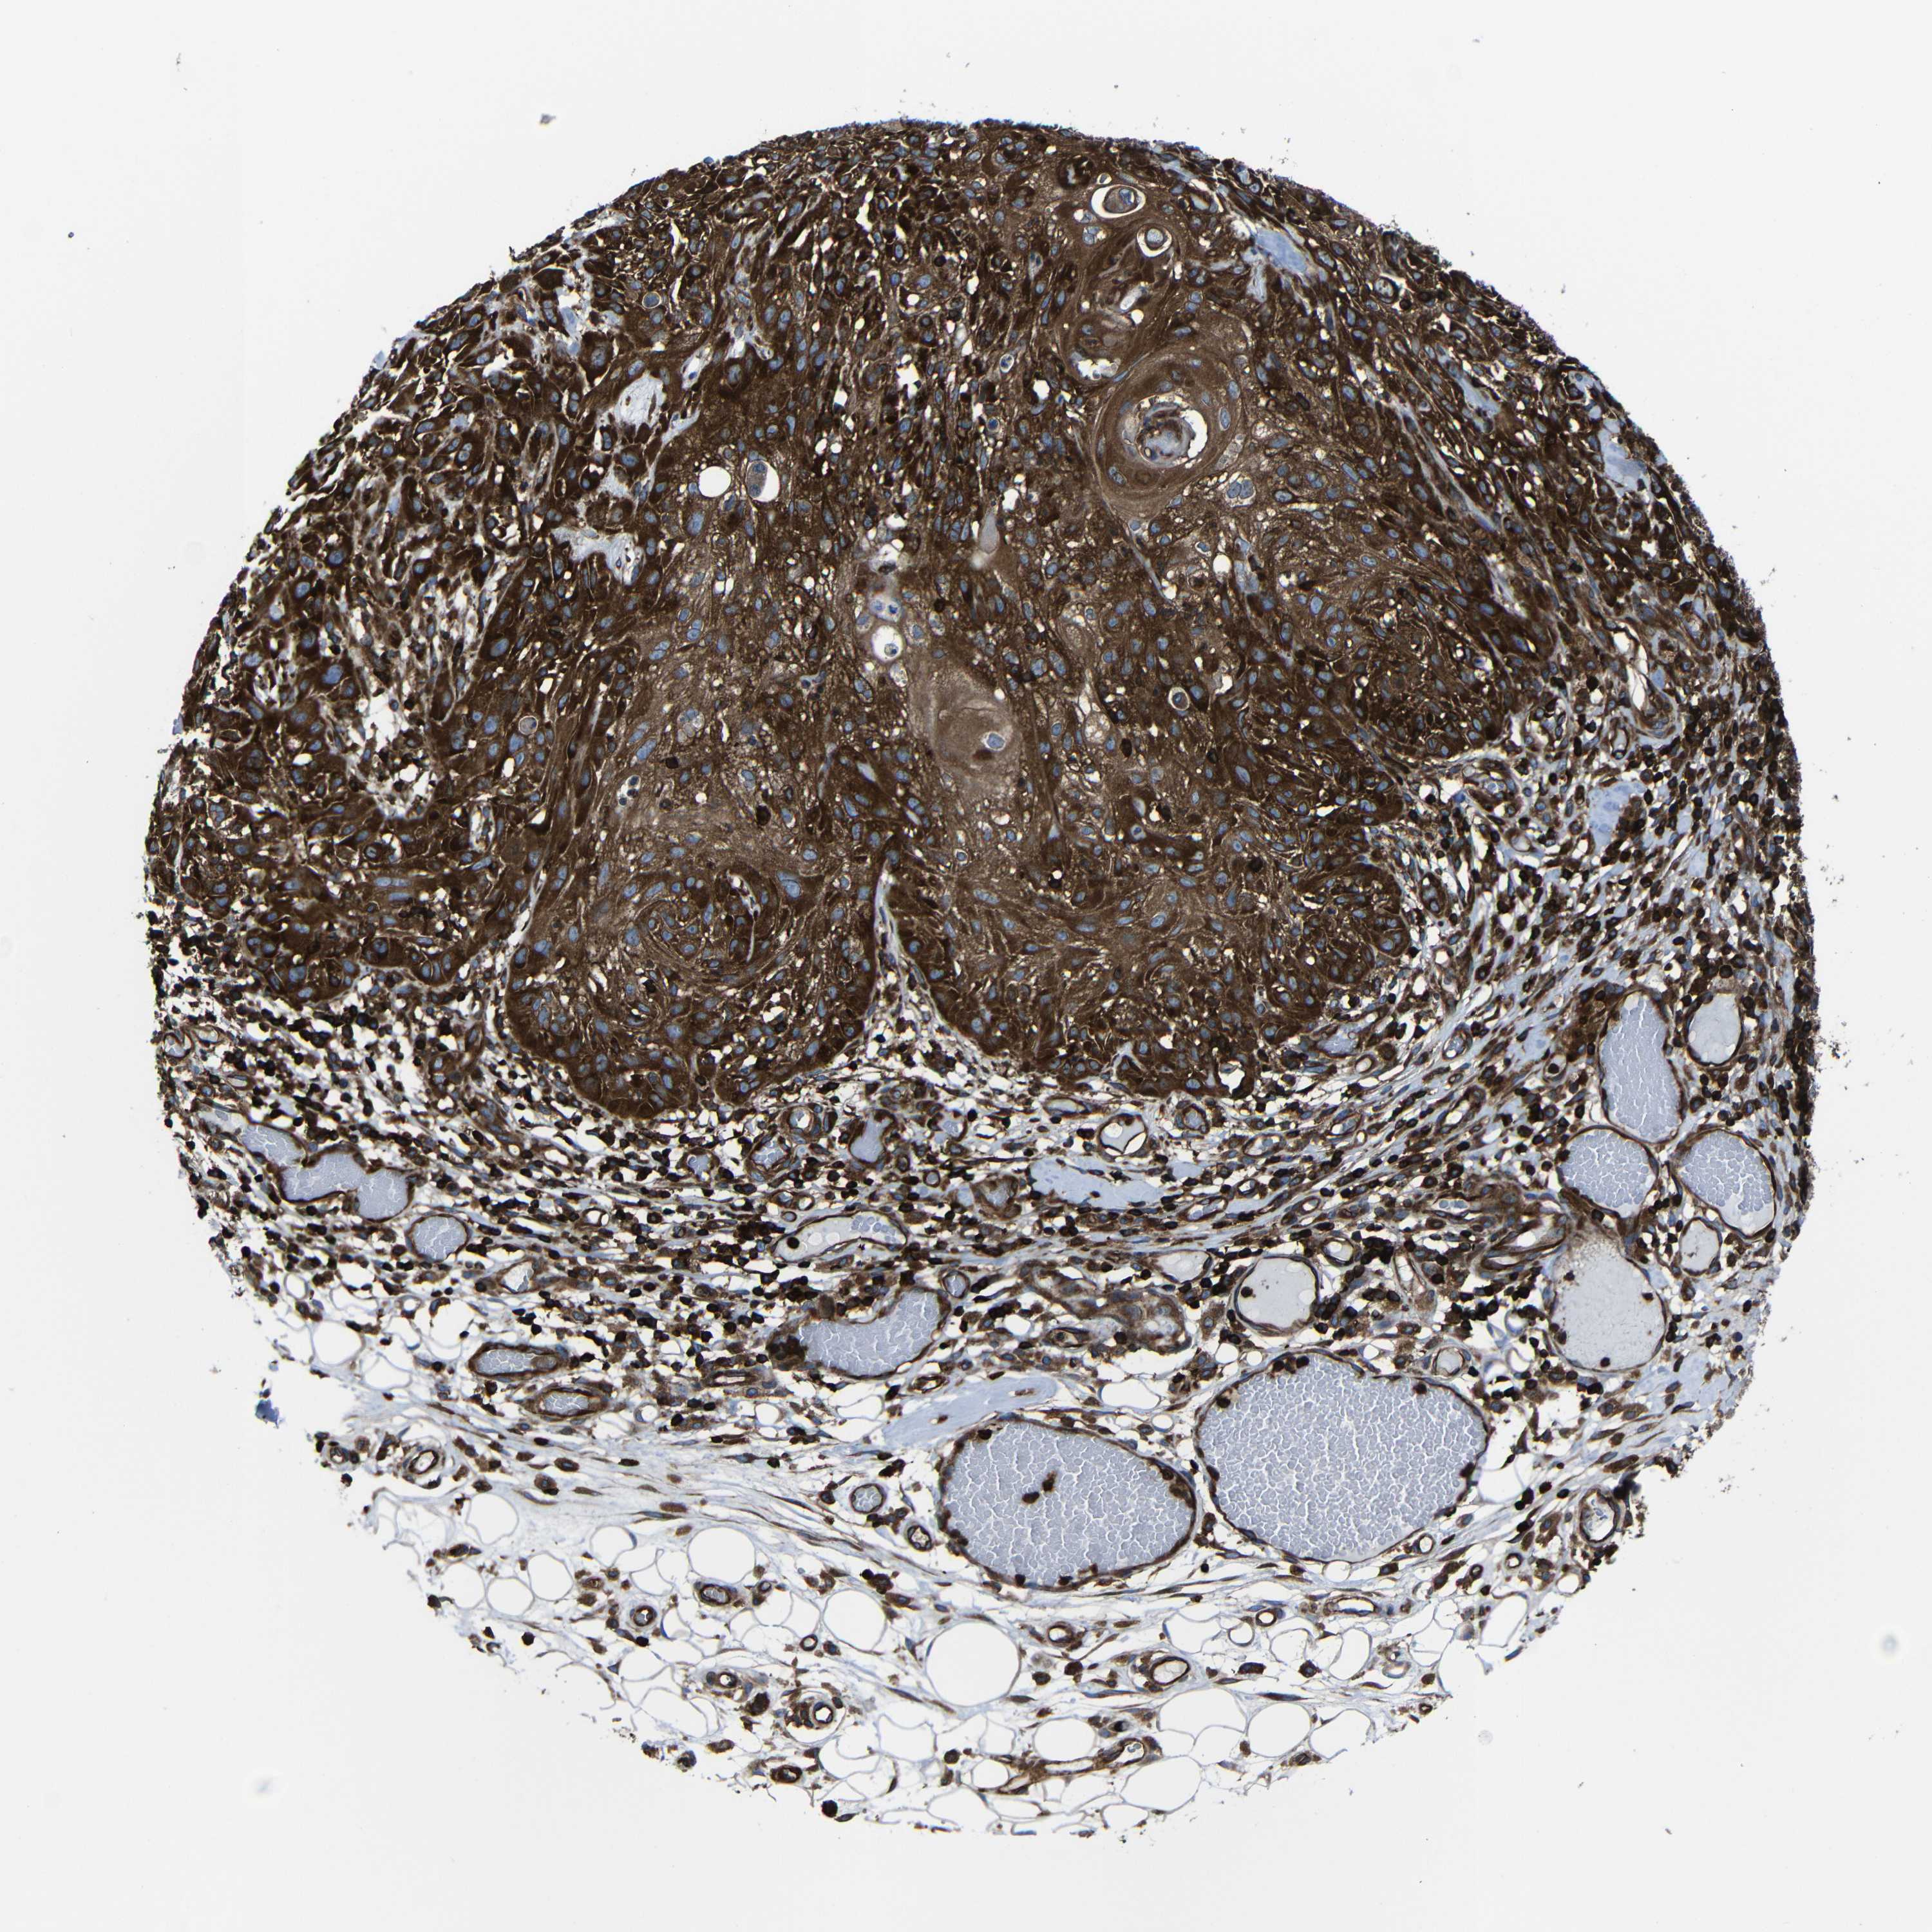

SKIN CANCER - Protein expressioni

A mouse-over function shows sample information and annotation data. Click on an image to view it in a full screen mode. Samples can be filtered based on level of antibody staining by selecting one or several of the following categories: high, medium, low and not detected. The assay and annotation is described here.

Each image is clickable and will lead to virtual microscopy that enables deeper exploration of all samples and also displays staining intensity scores, fraction scores and subcellular localization as well as patient and tissue information for each sample.

Antibody CAB009502

Basal cell carcinoma